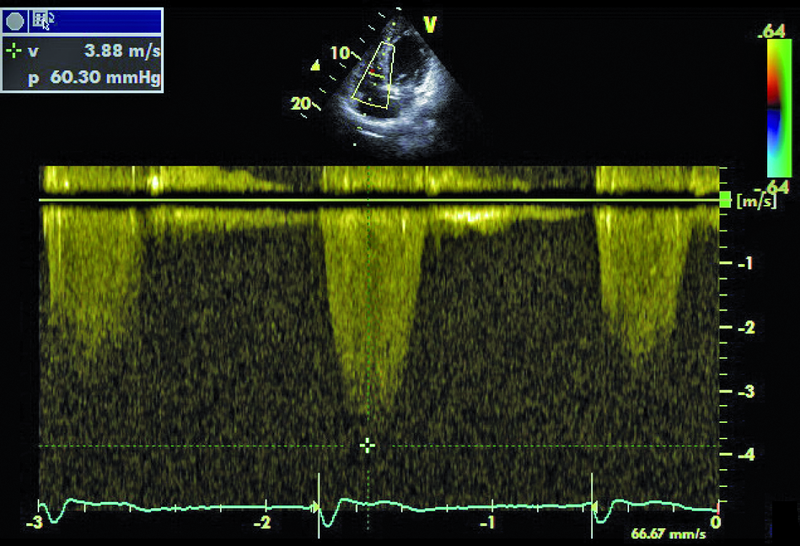

Niedomykalność zastawki mitralnej o etiologii niedokrwiennej pogarsza rokowanie u chorego z chorobą wieńcową i istotnie obniża komfort życia. Fala zwrotna w prezentowanym materiale sięga ujścia żył płucnych (ryc. 1), a ciśnienie w jamie prawej komory jest podwyższone (ryc. 2). U chorych, u których nie ma wskazań do rewaskularyzacji lub u chorych z chorobami współistniejącymi poszukuje się innych metod interwencji poza chirurgiczną naprawą. Punktem wyjścia dla rozważań o możliwości leczenia niechirurgicznego jest dokładna ocena anatomii zastawki. Wykorzystuje się dane zarówno z badania przezklatkowego, jak i przezprzełykowego, choć oczywiście optymalnym rozwiązaniem byłoby zastosowanie obrazowania trójwymiarowego. Sporo uwagi poświęca się ostatnio naprawie płatków zastawki za pomocą tzw. urządzenia mitraclip. Techniką tą można interesować się zwłaszcza w kontekście chorych bez istotnego poszerzenia pierścienia zastawki (w prezentowanym przypadku średnica pierścienia nie przekraczała 35 mm), a z dostatecznie dużą ilością tkanki tworzącej jej płatki. Założeniem techniki mitraclip, przypominającej zabieg chirurgiczny Alfieriego, jest połączenie segmentów środkowych płatka przedniego i tylnego. Skutecznie wykonany zabieg poprawia koaptację płatków i zapoczątkowuje odwrotny remodeling lewej komory, zmniejszający z kolei udział tzw. sił pociągających. Na co trzeba zwrócić uwagę, oceniając pacjenta z niedomykalnością mitralną, towarzyszącą chorobie niedokrwiennej? Niedomykalność (wg podziału Carpentiera typ 3b) powinna rzeczywiście powstawać między segmentami A2 a P2 (ryc. 3), ponieważ tylko w takim wypadku połączenie płatków i wytworzenie dwóch osobnych ujść może choremu przynieść korzyść. Ważnym elementem oceny jest uzyskanie projekcji przezżołądkowej poprzecznej. Ta projekcja bardzo dobrze ilustruje wielkość płatków i ich wzajemną relację (ryc. 4 – większy płatek tylny znajduje się bliżej głowicy). Przeciwwskazaniami do zabiegu implantacji mitraclip może być nadmierna grubość płatków, utrudniająca ich uchwycenie przez ramiona urządzenia, mniejsza niż 2 mm długość koaptacji oraz większa niż 11 mm głębokość koaptacji w stosunku do linii podstawnej pierścienia zastawki. Wymienionych cech nie potwierdzono w badaniu (ryc. 5, 6) i zakwalifikowano chorego do zabiegu w trybie planowym. Warto pamiętać, że echokardiografia służy nie tylko ocenie wskazań do zabiegu, ale stanowi także podstawę jego monitorowania.